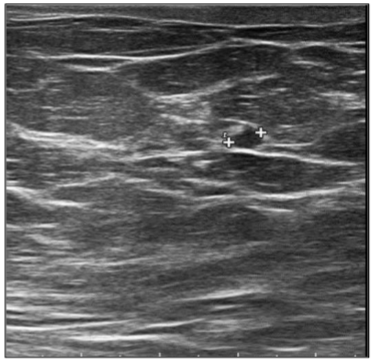

In September 2019, a 69-year-old woman presented to the emergency department of the University Hospital Città della Salute e della Scienza – Turin (Italy), reporting extreme fatigue and dyspnea. She had no comorbidities except for a medical history of papillary thyroid cancer, treated with thyroidectomy and radiotherapy 13 years before. Her complete blood count revealed anemia, thrombocytopenia and leukocytosis (Hb: 7.8 g/dL, PLT: 37 × 109/L, WBC: 45 × 109/L), while her physical examination was normal. The bone marrow smear showed 84% of blasts with myeloid immunophenotype (CD45, CD13, CD33, HLA-DR, lysozyme, CD36, CD64, CD11bc, partial CD14, and CD4 positive), molecular biology showed NPM1 mutation and FLT3-ITD positivity, while karyotype was normal (46, XX, 20/20). Consequently, a diagnosis of FLT3-ITD+ and NPM1 mutated t-AML was made. Induction chemotherapy was started with CPX-351 (liposomal daunorubicin 44 mg/m2 and cytarabine 100 mg/m2), obtaining CR with a 3-log NPM1 reduction (0.177). She was consolidated with CPX-351 (liposomal daunorubicin 29 mg/m2 and cytarabine 65 mg/m2 day 1 and 3), remaining in CR with persistent low level of measurable residual disease (MRD), NPM1 0.34. Meanwhile, we found a suitable HLA matched donor, but the patient refused the transplant procedure. Thus, we decided to start off-label azacitidine as maintenance therapy (50 mg/m2 subcutaneous daily for 5 days, every 28 days). Maintenance therapy was globally well tolerated, and the patient experienced only positivity for COVID-19 without need of hospitalization or additional care. She remained in CR with persistent MRD in BM (NPM1 0.044 after 12 cycles). During the fifteen course (May 2021), we found a palpable right mammary nodule on physical examination, confirmed on ultrasound, with a diameter of 18 x 11 mm. We stopped azacitidine and we promptly biopsied the nodule with a diagnosis of breast infiltration by AML blasts carrying the NPM1 mutation. CT scan and PET of chest, neck and abdomen were negative, and BM evaluation showed 1% blasts, with NPM1 0.044. The FLT3-ITD mutation resulted positive on breast cells while negative on medullary blasts. Thus, concluding for extramedullary relapse of AML FLT3-ITD mutated, we decided to start gilteritinib as single agent, at a dose of 120 mg daily. After 30 days, mammary ultrasound showed a reduction in diameter of the nodule, and in 4 months, the lesion has completely disappeared. The PET scan performed after 5 months of treatment was persistently negative and confirmed the absence of other uptakes. BM re-evaluation showed no blasts, with NPM1 0.006. Today, after 44 months of treatment, our patient is still in CR without signs of clinical and radiologic relapse. We continue monitoring her MRD status every two months on peripheral blood, as shown in table 1. Globally, therapy has been always well tolerated. In January 2024, we had to stop gilteritinib for 28 days due to pyelonephritis and sepsis treated with broad spectrum antibiotics. During this time, she remained in complete remission without any sign of relapse. After some months, in September, our patient has undergone exeresis of basal cell carcinoma, without complications and without need of stopping gilteritinib.